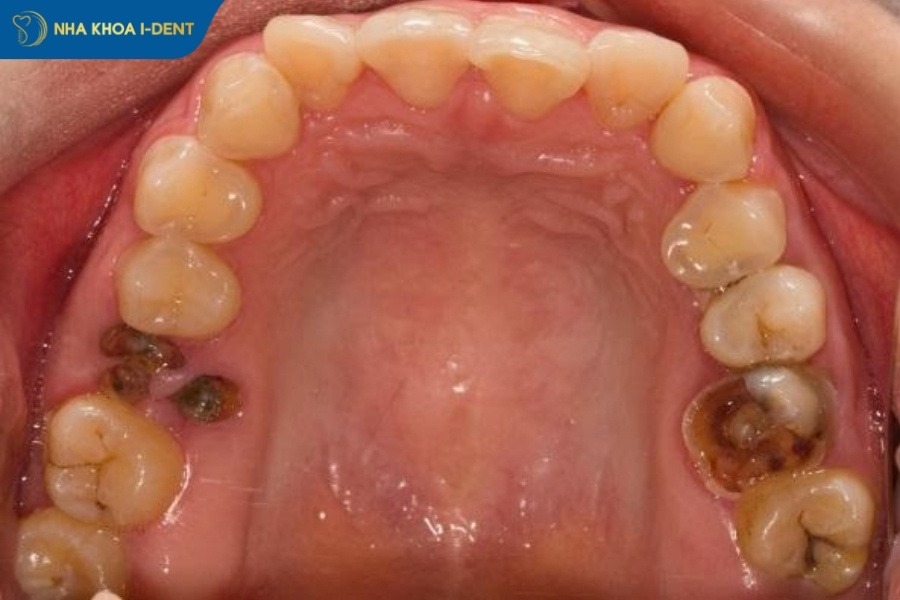

3. Khi nào cần bắt buộc nhổ răng sâu?

Nhổ răng sâu là kỹ thuật cơ bản trong nha khoa mà bác sĩ sẽ dùng dụng cụ chuyên dụng để tách răng ra khỏi xương hàm. Tuy nhiên, không phải trường hợp răng sâu nào cũng cần nhổ mà sẽ cần bác sĩ chỉ định. Trước khi nhổ răng sâu, bác sĩ sẽ kiểm tra, đánh giá mức độ sâu có phù hợp để nhổ răng hay không.

Các trường hợp răng sâu cần nhổ răng được bác sĩ chỉ định gồm:

- Răng sâu hoàn toàn: Vi khuẩn sâu răng tấn công và phá hủy toàn bộ mô răng, gây viêm tủy và vùng quanh chóp răng. Lúc này, việc nhổ răng sẽ ngăn chặn cơn đau và ngăn lan rộng ra các vùng khác.

- Răng gãy ngang sát nướu: Răng gãy ngang sát nướu được bác sĩ chỉ định nhổ bỏ để tránh làm tổn thương chân răng và sức khỏe răng miệng.

- Răng bị viêm tủy nặng: Răng viêm tủy nặng gây ra các biến chứng nghiêm trọng và không thể bảo tồn sẽ được bác sĩ chỉ định nhổ bỏ.

- Răng bị áp xe nhiễm trùng nghiêm trọng: Trường hợp răng bị áp xe cần nhổ bỏ để tránh triệu chứng đau đớn và nặng nề hơn.

Răng sâu hoàn toàn cần nhổ bỏ để ngăn chặn cơn đau và các biến chứng khác.